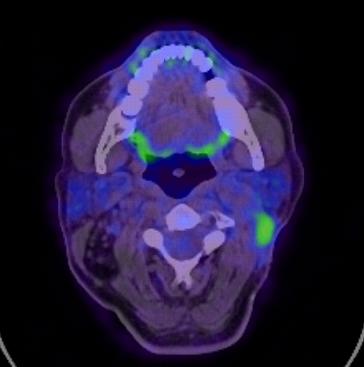

Pet tac cuello.